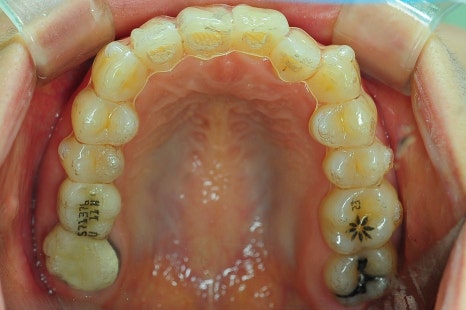

상악, 하악 각각 첫 번째 소구치를 발치했고,

인비절라인을 통해 치아를 뒤로 이동시키며 돌출을 점진적으로 개선했습니다.

뻐드러져 있던 치아 배열 모습이 정상적으로 돌아온 걸 확인하실 수 있을 겁니다.

총 치료 기간은 약 20개월이 걸렸는데요.